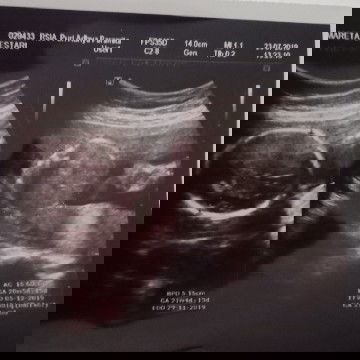

usg

Alhamdulilah td pas usg dedekny sehat . Tp kta dokter ari* ny dimulut rahim ktanya klok 2 bln lagi gk brubah posisi gk bisa lahiran normal bun. Ada yg kya sya gk bun trs hrs gmna ya